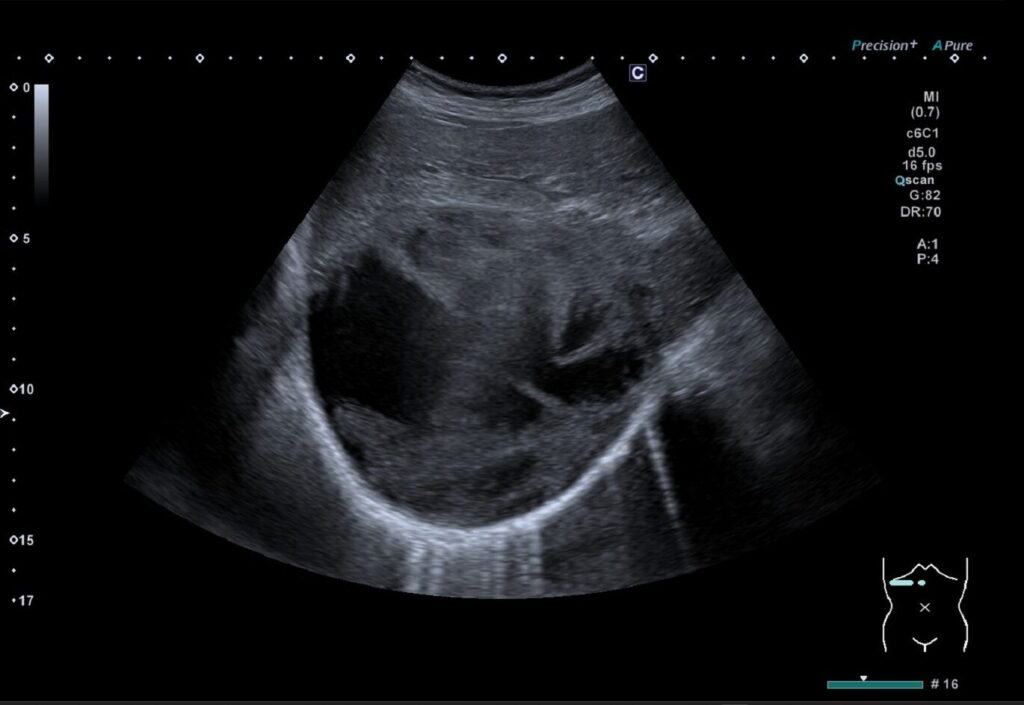

② 内部に点状エコーやモヤモヤエコーがある場合

- 出血や感染の可能性:内部点状高エコー、モヤモヤエコー(フィブリン析出)や膿が見られることがある。

- 観察の工夫:周波数、ゲイン、フォーカスを調整し、内部構造を詳細に観察する。

実際にみるとこんな感じです。

普段みている嚢胞とは違ってちょっとビックリしますよね。

内部一部が拍動によって揺らいでいるようにみえました。